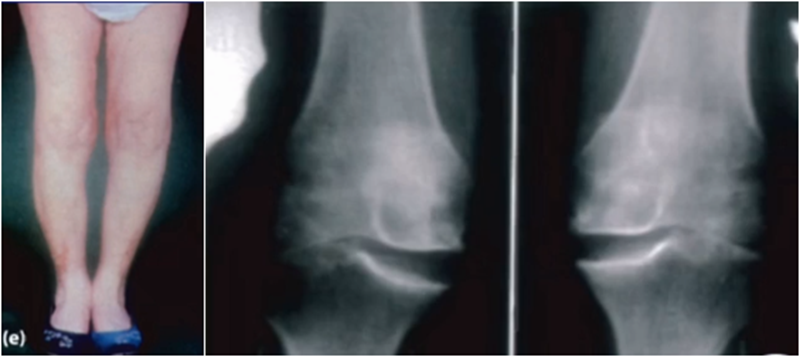

AMOA查体与X线特点,站立位屈曲内翻

AMOA的X线正位的表现